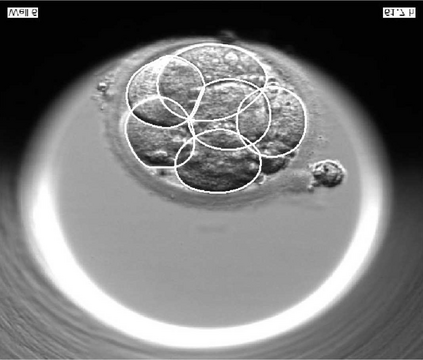

We present a novel method for identification of the boundary of embryonic cells (blastomeres) in Hoffman Modulation Contrast (HMC) microscopic images that are taken between day one to day three. Identification of boundaries of blastomeres is a challenging task, especially in the cases containing four or more cells. This is because these cells are bundled up tightly inside an embryo's membrane and any 2D image projection of such 3D embryo includes cell overlaps, occlusions, and projection ambiguities. Moreover, human embryos include fragmentation, which does not conform to any specific patterns or shape. Here we developed a model-based iterative approach, in which blastomeres are modeled as ellipses that conform to the local image features, such as edges and normals. In an iterative process, each image feature contributes only to one candidate and is removed upon being associated to a model candidate. We have tested the proposed algorithm on an image dataset comprising of 468 human embryos obtained from different sources. An overall Precision, Sensitivity and Overall Quality (OQ) of 92%, 88% and 83% are achieved.